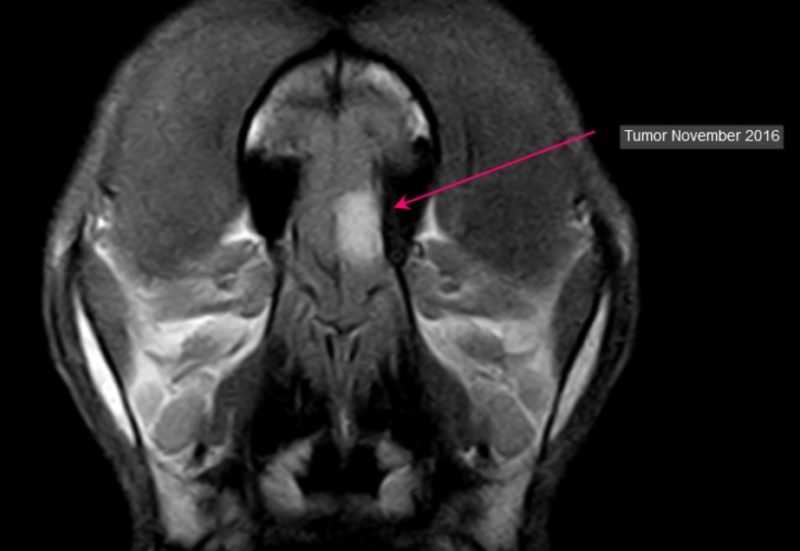

Des weiteren wurde Ghamina zu einer MRT-Untersuchung des Gehirns überwiesen. Der Befund bestätigte den Verdacht, es wurde ein flächiger Tumor im linken Riechhirn diagnostiziert. Aufgrund der typischen Kontrastmittelaufnahme bestand Verdacht auf ein Meningeom - ein Tumor, der von den Hirnhäuten ausgeht. Es zeigte sich eine mäßige Wasseransammlung (Ödem) um den Prozess. Um diese zu verringern und auch, da die Wachstumstendenz von Meningeomen positiv beeinflusst wird, erhielt Ghamina zusätzlich zum Antiepielptikum ein Kortison. Eine Operation, die aufgrund der Lokalisation und Ausdehnung schwierig gewesen wäre, kam für die Besitzerin nicht in Betracht.

Im November 2016 wurde ein Folge-MRT angefertigt. Das Meningeom hatte sich minimal um ca. 1 mm in jede Richtung ausgedehnt. Symptome zeigten sich am Hund dagegen nicht. Zu Weihnachten erfreute sich die Besitzerin an einem scheinbar völlig gesunden, 12-jährigen Rhodesian Ridgeback-Hündin - sie feierte die sechs Monate Lebensfreude seit der Diagnose!